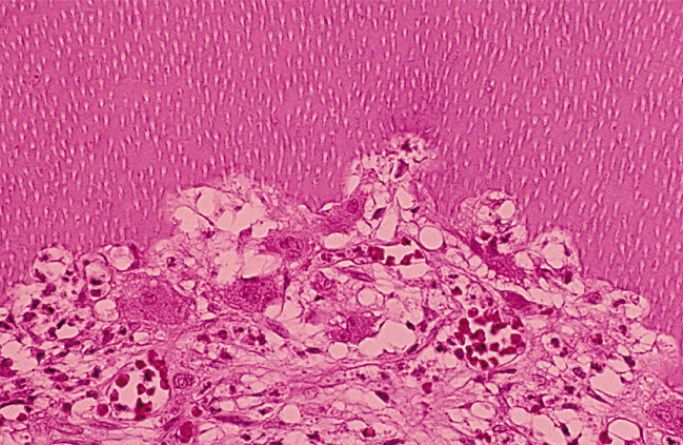

Internal resorption histopathology

Resorption of the inner dentinal wall of the pulp. Note cellular and vascular fibrous connective tissue, which exhibits an adjacent inflammatory infiltrate and numerous dentinoclasts within resorptive lacunae